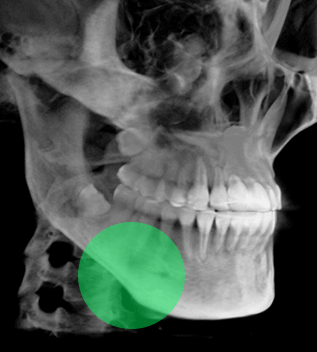

광대뼈는 사각턱뼈에 비해 작고 약하고 얇으며, 얼굴뼈 중에서 가장 강한 힘을 받기 때문에 광대뼈 축소수술은

안면윤곽 수술 중에서 가장 어려운 수술입니다. 김태규 대표원장이 직접 개발한 리프팅 3D 광대회전술은

브라운만의 우수한 기술력을 통해 안전하고 효과적인 광대 축소술이 가능 합니다.

실제 수술환자 CT 전후사진

광대뼈는 사각턱뼈에 비해 작고 약하고 얇으며,

얼굴뼈 중에서 가장 강한 힘을 받기 때문에

광대뼈 축소수술은 안면윤곽 수술 중에서 가장 어려운 수술입니다.

김태규 대표원장이 직접 개발한 리프팅 3D 광대회전술은 브라운만의

우수한 기술력을 통해 안전하고 효과적인 광대 축소술이 가능합니다.